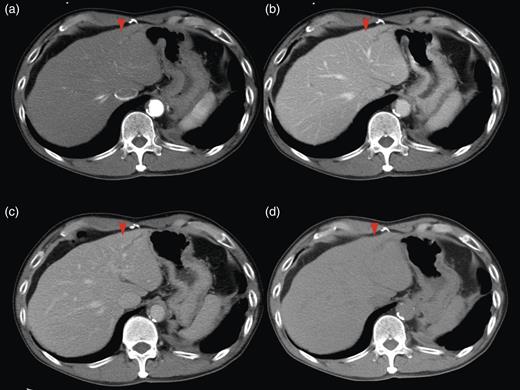

Computed tomography (CT) demonstrated two solitary lesions in segment (S) eight. Furthermore, S3 hepatic duct dilatation was clearly detected on CT scanning (Fig. 1).